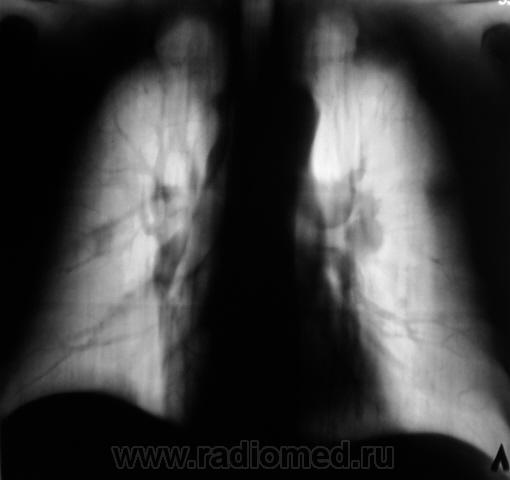

Пациент "взят на контроль" при расшифровке цифровых флюорограмм, дообследован - рентгенография в стандартных проекциях. Ваше мнение коллеги?

Произведены томограммы.

Пахнет периферическим c-r SIII лев. л-го, хотя на ТМГ он не получил должного отображения. Mts в лимфатич. узлы корня. Очаговые тени в легких вроде как связаны с сосудами...

MTS в правое и левое лёгкие, лимфатические узлы левого корня.

Это контроль после флюорографии. Рентгенологически выставлен метастатический процесс, рекомендована консультация онколога, но что-то тянут коллеги. Сам "инфильтрацию" расцениваю, как параканкрозную пневмонию. А боковой и томограммы в начале случая. Времени от "первых" снимков прошло 3 дня.

Пациенту произведена МРТ головного могза - множественные метастазы.

Выставляю флюорограмму за 2009 год.